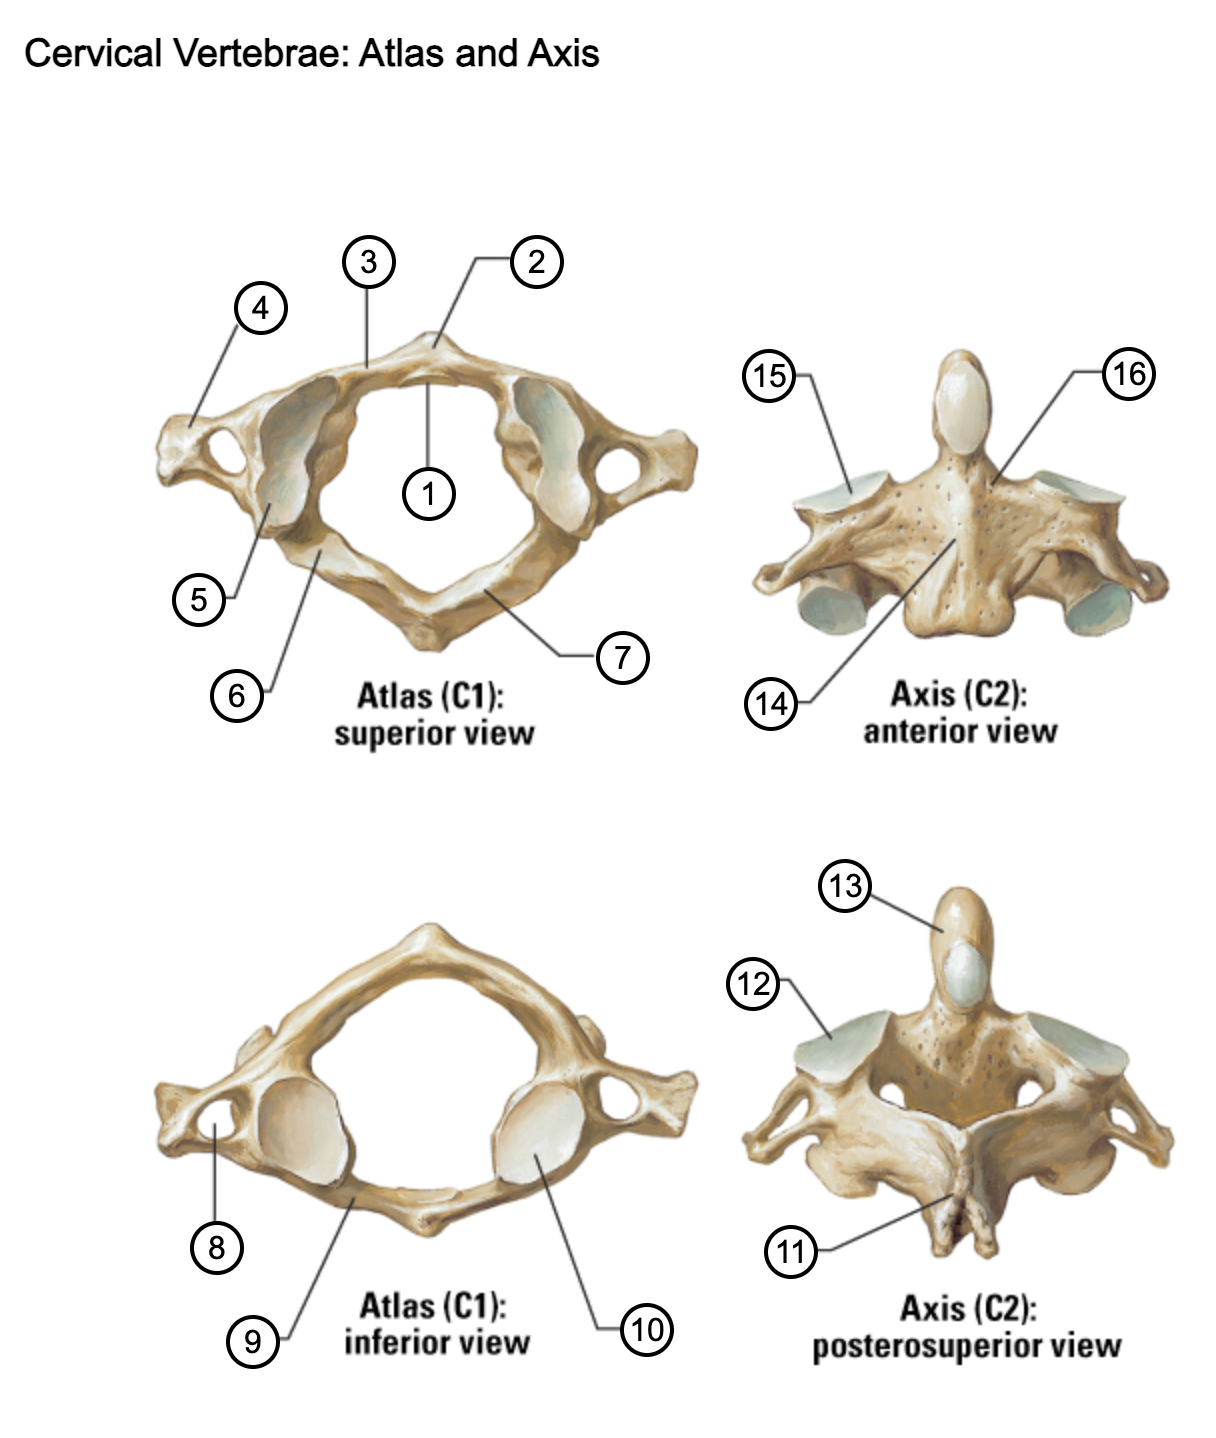

1

facet for dens

2

anterior tubercle

3

anterior arch

4

transverse process

5

superior articular surface of atlas

6

groove for vertebral artery

7

posterior arch

8

transverse foramen

9

anterior arch

10

inferior articular surface of atlas

11

spinous process

12

superior articular facet

13

dens of axis

14

body of axis

15

superior articular facet for atlas

16

pedicle of vertebral arch